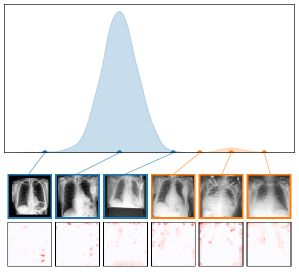

We further plot the distribution of CAV-based bias scores for biased and clean samples for the real-world artifacts ruler (ISIC2019) and pacemaker (CheXpert) in Fig. 8. We compute bias scores using the best performing CAV per artifact and use latent activations after the residual block of the ResNet50 model for ruler, and the convolutional layer of the VGG16 model for pacemaker. We show samples corresponding to the bias score in the top-1 and -99 percentiles of each set. Samples near the decision boundary are particularly interesting, as they may arise from labeling errors. Both examples demonstrate the retrieval of unlabeled artifact samples. The distributions of bias scores for additional artifacts are shown in Appendix A.6.2.